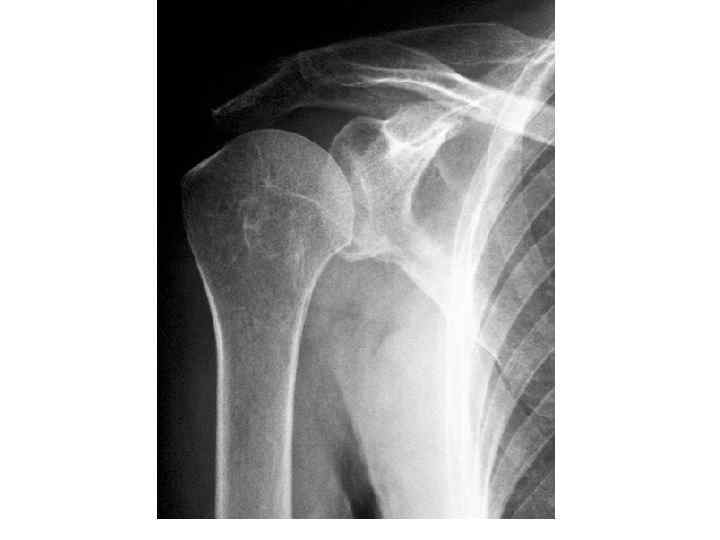

Головка плечевой кости в задней проэкции с вытянутой вдоль туловища конечностью, своей нижнемедиальной частью наслаивается на суставную впадину лопатки и проэцируется всегда выше нижней границы ее. Знание этой ретнгенологической нормы помогает распознать вывихи.

Головка плечевой кости в задней проэкции с вытянутой вдоль туловища конечностью, своей нижнемедиальной частью наслаивается на суставную впадину лопатки и проэцируется всегда выше нижней границы ее. Знание этой ретнгенологической нормы помогает распознать вывихи.

ПЛЕЧЕВОЙ СУСТАВ - появление двух т. о. в головке плечевой кости - 9 -12 мес - син-ие всех т. о в единую головку – 5 -8 лет - син-ие эпифиза и диафиза - 20 -23 года - появление множественных т. о. по краю суставной впадины лопатки – 4, 5 -5 лет - син-ие т. о. края суставной впадины – 67 лет

ПЛЕЧЕВОЙ СУСТАВ - появление двух т. о. в головке плечевой кости - 9 -12 мес - син-ие всех т. о в единую головку – 5 -8 лет - син-ие эпифиза и диафиза - 20 -23 года - появление множественных т. о. по краю суставной впадины лопатки – 4, 5 -5 лет - син-ие т. о. края суставной впадины – 67 лет